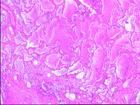

腫塊常較大,一般直徑5~10cm,亦有達15cm 者。呈結節狀或分葉狀,表面常有一層假包膜,切面呈脂黃色,黏液樣或魚肉樣,常有出血、壞死。鏡檢可見不同分化程度的脂母細胞,形態大小不一,星形、梭形、圓形、“印戒狀”等。脂滴空泡邊界清楚,圓而光滑,完全透明。空泡大時常擠壓核至邊緣或呈扇貝狀。在多形性脂肪肉瘤中常見巨大畸形多空泡脂母細胞。黏液樣脂肪肉瘤中除脂母細胞和黏液樣基質外,可見纖細的叢狀毛細血管網。瘤細胞間可有淡藍色黏液和脂肪滴。

脂肪染色(油紅O、蘇丹、猩紅等)常陽性。免疫組化染色S-100 不規則陽性。黏液樣型脂肪肉瘤,部分分化良好型和多形性脂肪肉瘤中均能檢測到特徵性的染色體易位t(12;16)(q13;p11),或用RT-PCR,DNA 點雜交可檢測到由於染色體易位而形成的FUS/TLS-CHOP 嵌合轉錄。